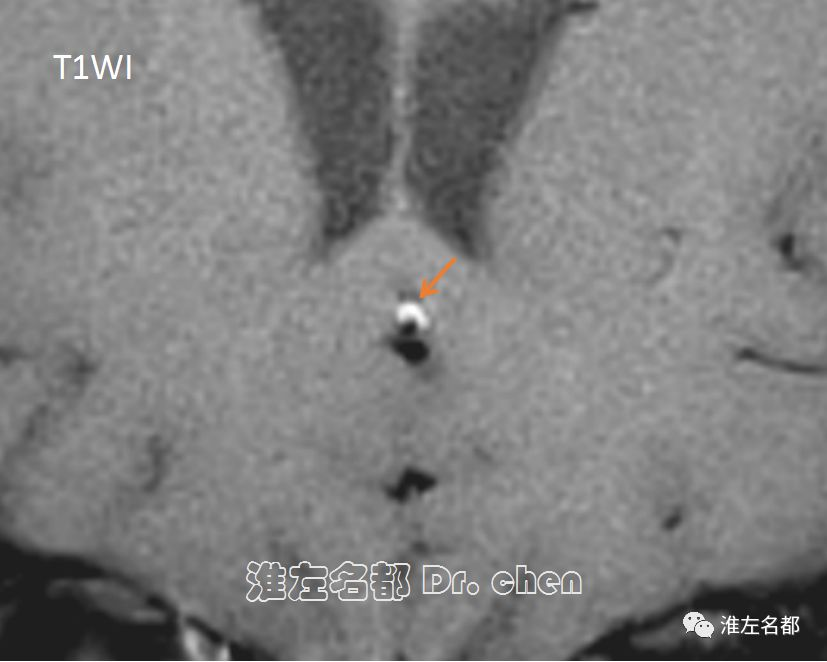

△管壁高分辨MRI之T1WI和T2WI序列:左侧大脑前动脉A2段可见“月牙形”壁内血肿高信号(亚急性期),提示动脉夹层